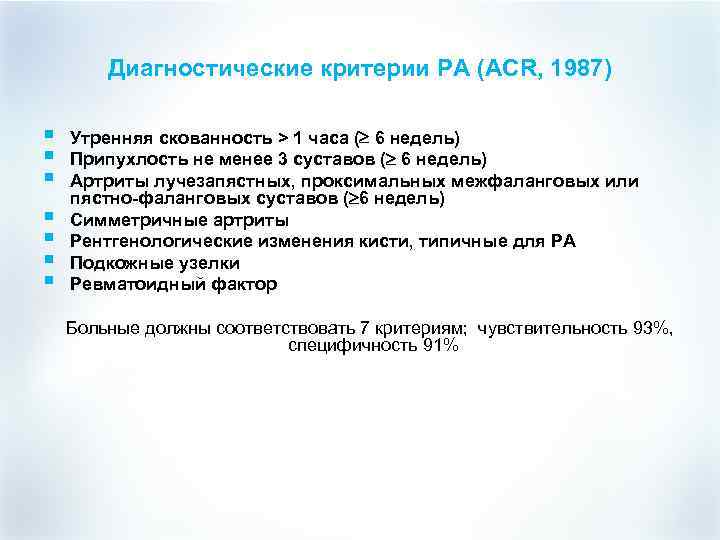

Диагностические критерии РА (ACR, 1987) § § § § Утренняя скованность > 1 часа ( 6 недель) Припухлость не менее 3 суставов ( 6 недель) Артриты лучезапястных, проксимальных межфаланговых или пястно-фаланговых суставов ( 6 недель) Симметричные артриты Рентгенологические изменения кисти, типичные для РА Подкожные узелки Ревматоидный фактор Больные должны соответствовать 7 критериям; чувствительность 93%, специфичность 91%

Диагностические критерии РА (ACR, 1987) § § § § Утренняя скованность > 1 часа ( 6 недель) Припухлость не менее 3 суставов ( 6 недель) Артриты лучезапястных, проксимальных межфаланговых или пястно-фаланговых суставов ( 6 недель) Симметричные артриты Рентгенологические изменения кисти, типичные для РА Подкожные узелки Ревматоидный фактор Больные должны соответствовать 7 критериям; чувствительность 93%, специфичность 91%